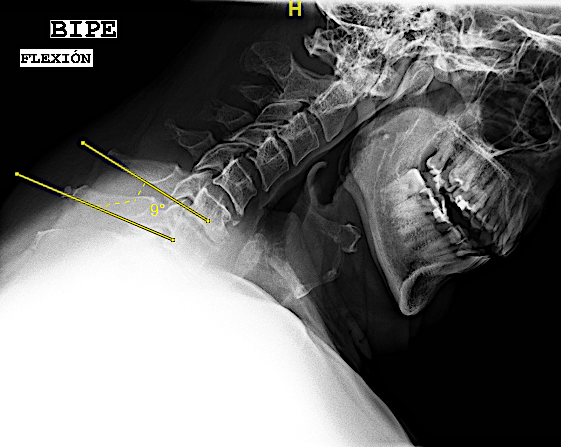

- «fijación intersomática» cuando en las RX funcionales no se aprecia movimiento sin ver «puentes óseos». Puede valer para este apartado el criterio de hallar una diferencia de <1mm entre la distancia de las respectivas apófisis espinosas en flexo/extensión o, si las espinosas no se visualizan o no están presentes, una angulación de platillos <3º también en las RX dinámicas. A estos pacientes les realizo un seguimiento anual con Rx (hasta visualizar puentes óseos o durante 3 años).

Las RX dinámicas demuestran fijación intersomática sin puentes óseos todavía. Obsérvese la recuperación del espacio intersomático respecto al preoperatorio, (indicativo de estabilidad de la artrodesis). El paciente, a los 6 meses de la cirugía, refiere crisis frecuentes de cervicalgias mecánicas altas bien controladas con analgesia de primer nivel y reposo relativo (ha dejado mórficos) y resolución de la braquialgia izquierda.